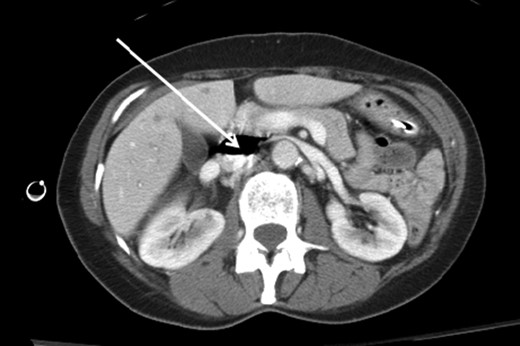

A 66-year-old female patient presented to our level I trauma center after a motor vehicle collision. She sustained multiple injuries including several fractured ribs, hemopneumothorax and a right diaphragmatic rupture. She was hemodynamically normal during her primary and secondary survey, and received a right femoral vein central venous catheter (CVC) for fluid resuscitation. She underwent computed tomography (CT) scan for further diagnostic evaluation and was noted to have the aforementioned injuries and a significant amount of air within the IVC, right iliac and femoral veins (Figs. 1–3). She was immediately placed in Trendelenburg position; a new subclavian CVC was inserted and used to withdraw air. Her right femoral vein introducer was suspected to be the source and was removed. She remained stable with no obvious clinical sequelae and underwent operative repair of her diaphragmatic injury. The patient was discharged on hospital Day 10 with no issues.

Axial contrast-enhanced CT image of the abdomen demonstrating air within the IVC (arrow).